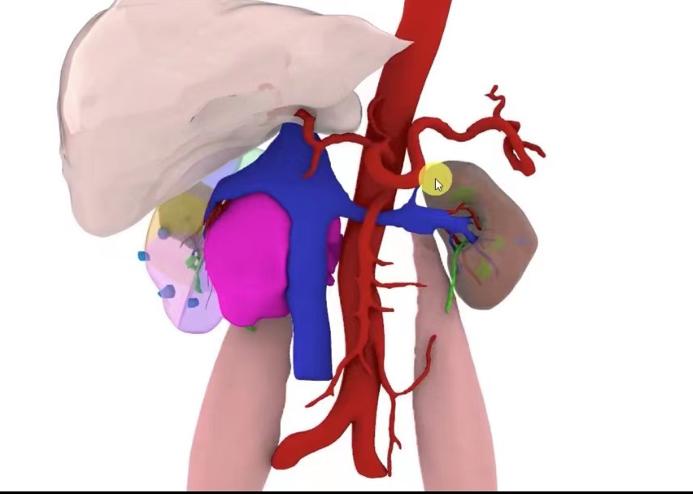

全息影像技术通过处理加工患者的CT及MRI影像数据资料,呈现出高保真的全息立体影像。通过全息影像,医生可以看清人体内部复杂器官的相对位置,清晰显示肿瘤与周围血管,器官的相对关系,全方位透视肿瘤,为术者在手术全程提供参照,大大缩短了手术时间,提高了手术安全性。

南医三院泌尿外科是目前广东省开展单孔腹腔镜技术最为成熟的单位,现又紧跟时代潮流,率先运用了全息影像与单孔腹腔镜影像融合技术,为该高龄复杂肾癌患者完成了单孔腹腔镜下右肾癌根治性切除术。该技术在肾癌根治性切除过程中,通过融合影像快速定位肿瘤的位置、边界以及血管分布情况,帮助手术医生更快更安全地切除了右肾癌及转移的淋巴结。